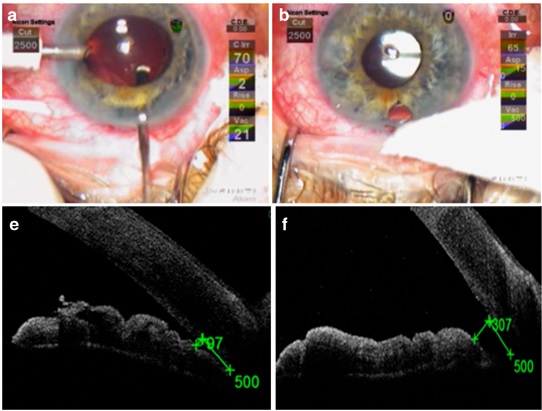

그래서 섬유주 절제술을 시행할 때, 주변부 홍채 절제술을 같이 시행하여,

홍채절제부위를 통해, 동공이외에 전방과 후방사이의 연결 통로를 만들어 주어,

수술후 염증발생으로 인한 동공차단을 예방하기 위함입니다.

하지만 이 홍채절제술 부위가 제대로되지 않았거나

홍재절제술이 시행되었더라도, 염증물질이나 유리체에 의해서 막힌경우에는,

수술후 발생한 염증에 의해 동공차단이 발생한 경우, 안압이 급격히 상승할수 있습니다.

홍채절제술부위가 충분히 개방되어 있지 않는 경우,

수술적으로 홍재절제술부위를 다시 개방해주거나 Nd:YAG레이저로 홍채절개술을 추가로 시행해줄수 있습니다.